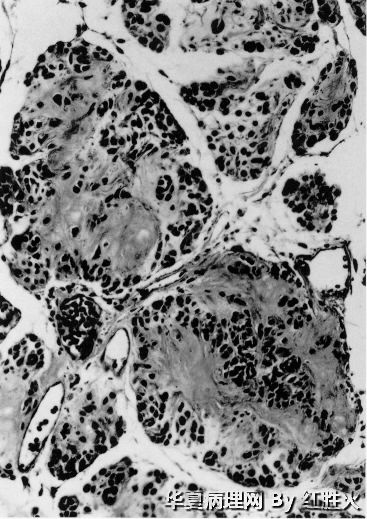

文献中描述的神经母细胞瘤样神经鞘瘤的组织学特点是具有巨大的菊形团结构,细胞呈淋巴细胞样,细胞浆稀少;部分病例也有上皮样特点区域。因此从形态描述上,神经母细胞样神经鞘瘤与上皮样神经鞘瘤有共同点,有时难以区分。但是从实际诊断的角度,应当抓住病变的主要特征,当以菊形团结构为主时,宜诊断神经母细胞瘤样神经鞘瘤,当以上皮样细胞为主时,宜诊断上皮样神经鞘瘤。本例以上皮样特点为主,所以宜诊断为上皮样神经鞘瘤。

经典型神经鞘瘤容易诊断,而多种特殊亚型(包括陈旧性或退变性神经鞘瘤;细胞性神经鞘瘤;丛状神经鞘瘤;上皮样神经鞘瘤;色素性神经鞘瘤;胃肠道型神经鞘瘤;腺样神经鞘瘤和假腺样神经鞘瘤;微囊状/网状型神经鞘瘤和神经母细胞瘤样神经鞘瘤等)少见或罕见,形态特殊,可造成诊断困难或未被认识,原野所提供的病例恰好可引起我们对此类肿瘤的重视,对开拓思路大有益处。文献报道的神经母细胞瘤样神经鞘瘤图像如下,供参考